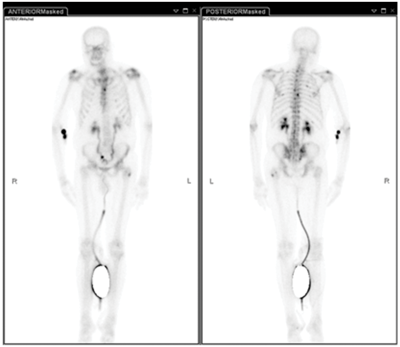

Case 1

-

MAG-3 renogram, obstructed left kidney likely secondary to (pelvi-ureteric junction obstruction) PUJO.

MAG-3: mercaptoacetyltriglycine attached to technetium 99m, half-life six hours. 90% tubular excretion, 10% filtered at the glomerulus.

20-30 minutes.

2.5-3mSv (Higher in Aberdeen / Cornwall, approximately 8mSv).

Approximately 0.5-0.7mSv.